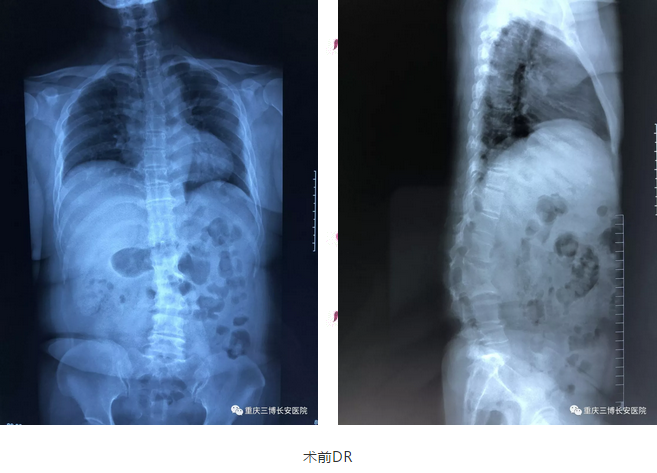

入院后,蒋某被诊断为脊柱侧弯后凸畸形、腰椎间盘突出、腰4、5椎间盘脱出、腰2、3椎体病理性融合。

2018年9月9日,在完善术前相关准备后,王忠平副院长携脊柱脊髓专科团队为蒋某行了脊柱矫形术。

术后,复查DR提示,蒋某脊柱畸形得到很好改善,恢复良好,下肢活动逐渐恢复。